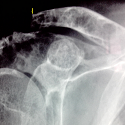

Le cubitus varus post traumatique

Karima Atarraf, My Abderrahmane Afifi

PAMJ. 2014; 19: 100. Published 29 September 2014